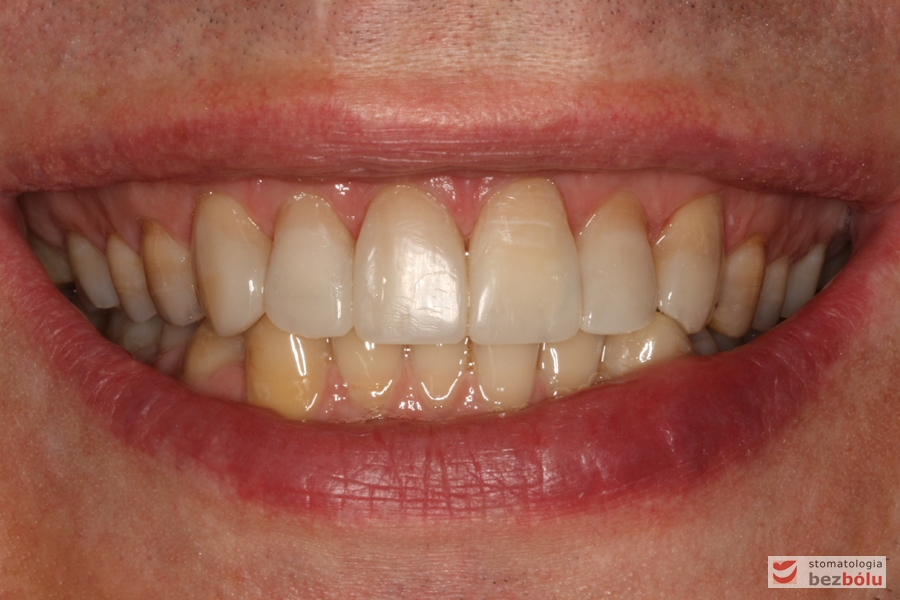

Uśmiech pacjenta - ekspozycja dziąsła w strefach bocznych, za długie zęby dolne przednie

Uśmiech pacjenta – ekspozycja dziąsła w strefach bocznych, za długie zęby dolne przednie